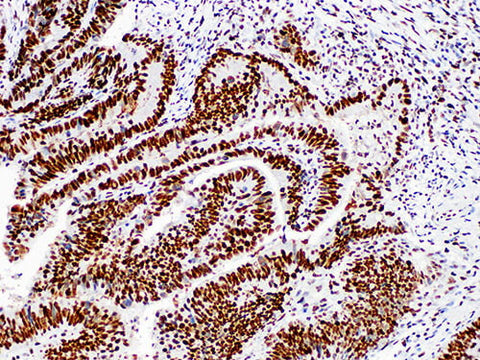

MSH2 Monoclonal Antibody Stored at 2~8°C

Applications IHC-P

Cellular Localization nucleus

Tissue Specificity Colon cancer

DNA mismatch repair (MMR) system is composed of enzyme molecules that specifically repair DNA base mismatch. The existence of this system can ensure the integrity and stability of genetic material, avoid the mutation of genetic material, and ensure the high fidelity of DNA replication. It is composed of hMLH1, hMSH2, hpms1, hPMS2 and other genes. HMSH2 is located in human chromosome 2p21-22, encoding a protein composed of 934 aa. The mutation of hMSH2 gene occurs in sporadic colorectal cancer. The mutation of microsatellite hMSH2 gene is related to 50% of familial and non-familial polyposis colorectal cancer (HNPCC).